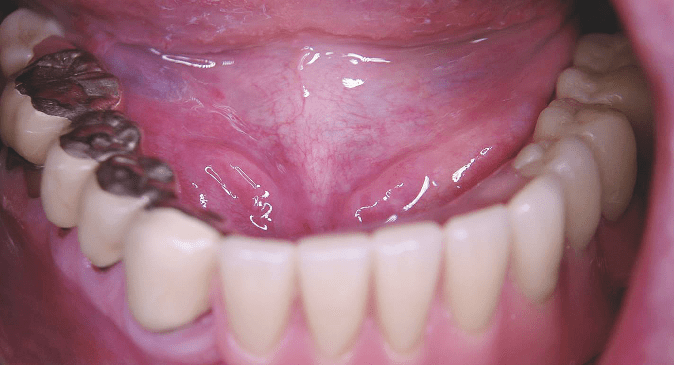

Im folgenden Patientenfall wird gezeigt, wie ein atrophierter, nach dorsal verlagerter Oberkiefer mit einer für eine konventionelle Versorgung statisch ungünstigen Restbezahnung durch die Insertion von Implantaten (ANKYLOS®, DENTSPLY Friadent, Mannheim, Deutschland) und präfabrizierten Konusaufbauten (SynCone®-System, DENTSPLY Friadent) auf einfache Weise wieder herausnehmbar versorgt werden kann. Im Oberkiefer des Patienten war eine Teilprothese nach der Extraktion von drei parodontal insuffizienten Zähnen nur noch auf drei Pfeilerzähnen mittels Teleskopen verankert (Abb. 4). Aufgrund der ungleichmäßigen Abstützung erwiesen sich der Prothesenhalt und die Lagestabilität der Prothese bei Kaubelastung als unzufriedenstellend. Der Patient fühlte sich in seiner Lebensqualität sowie in seiner Kau- und Sprechfähigkeit eingeschränkt. Er wünschte die Wiederherstellung einer gut sitzenden Prothese und eine gaumenfreie Versorgung.

Nach Abformung der Kiefer, 3-D-Diagnostik und Wax-up wurden die Versorgungsmöglichkeiten mit dem Patienten erörtert. Zur Auswahl standen neben der Insertion von drei Implantaten die Möglichkeiten einer Versorgung mit mehr als fünf Implantaten und einer fest­sitzenden implantatgetragenen Prothese oder fest­sitzende, implantatgetragene Einzelzahnkronen mit knöcherner Augmentation. Gemessen am hohen finanziellen und instrumentellen Aufwand für eine festsitzende implantatgestützte Restauration in Relation zu dem ­ge­ringen Zugewinn an oraler Lebensqualität und der ein­geschränkten Hygienefähigkeit wurde die Therapieentscheidung zugunsten einer herausnehmbaren Lösung auf den drei natürlichen Restzähnen und auf drei zusätzlich inserierten Implantaten getroffen. Ein weiterer Vorteil dieser Strategie besteht in der Erweiterbarkeit der prothetischen Suprakonstruktion im Falle zukünftiger Verluste natürlicher Zähne.

Die natürlichen Zähne wurden mit per CAD/CAM-Technik hergestellten Zirkoniumdioxidkeramik-Käppchen versehen (Abb. 5). Im gaumenfreien Oberkieferprothesengerüst konnte eine gemeinsame Einschubrichtung aller Sekundärteile umgesetzt werden (Abb. 6). Die neue herausnehmbare prothetische Lösung entsprach genau den anfänglich geäußerten Wünschen des Patienten nach einer lagestabilen, gaumenfrei gestalteten Versorgung (Abb. 7). Ähnliche Ansprüche stellte auch der Patient im zweiten hier vorgestellten Fall. Er war über lange Zeit mit einer ­Teleskoparbeit im Oberkiefer versorgt gewesen. Durch Verlust der Pfeilerzähne wurde ihm eine klassische Oberkieferprothese mit Gaumenabdeckung eingegliedert. Da der Patient leidenschaftlicher Weinkenner und -genießer ist, war diese neue Situation für ihn absolut inakzeptabel, die gaumenfreie Gestaltung der prothetischen Re­kons­truktion im Oberkiefer stand für ihn an erster Stelle. Die Herausforderung dieses Falles bestand in der richtigen Einschätzung der Situation: Bei isolierter Betrachtung des Oberkiefers zeigte sich sowohl klinisch als auch radiologisch ein suffizientes Knochenangebot, in dem sich relativ problemlos eine adäquate Anzahl an Implantaten verankern ließ. Kleinere Defekte konnten aufgefüllt und im Seitenzahngebiet durch interne Sinusbodenelevation das vertikale Knochenangebot verbessert werden. Das Ergebnis schien die Versorgung klar vorzugeben (Abb. 8): Offensichtlich kam nur eine fest­sitzende Rekonstruktion infrage.